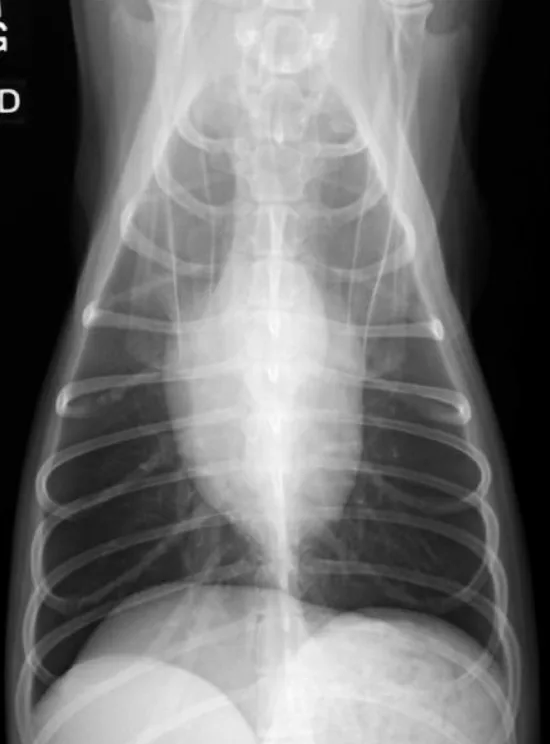

Step 2: Pleural Space

The pleural space should not be seen on thoracic images from normal animals. A very small amount of fluid, normally present between the visceral and parietal pleura, is imperceptible on thoracic radiographs; however, the pleural fissure lines or interlobar fissures may still be seen within very specific locations (Figure 3).

Right lateral (A) and ventrodorsal (B) radiographs from the same dog shown in Figure 2 with the expected locations of the interlobar fissures noted.